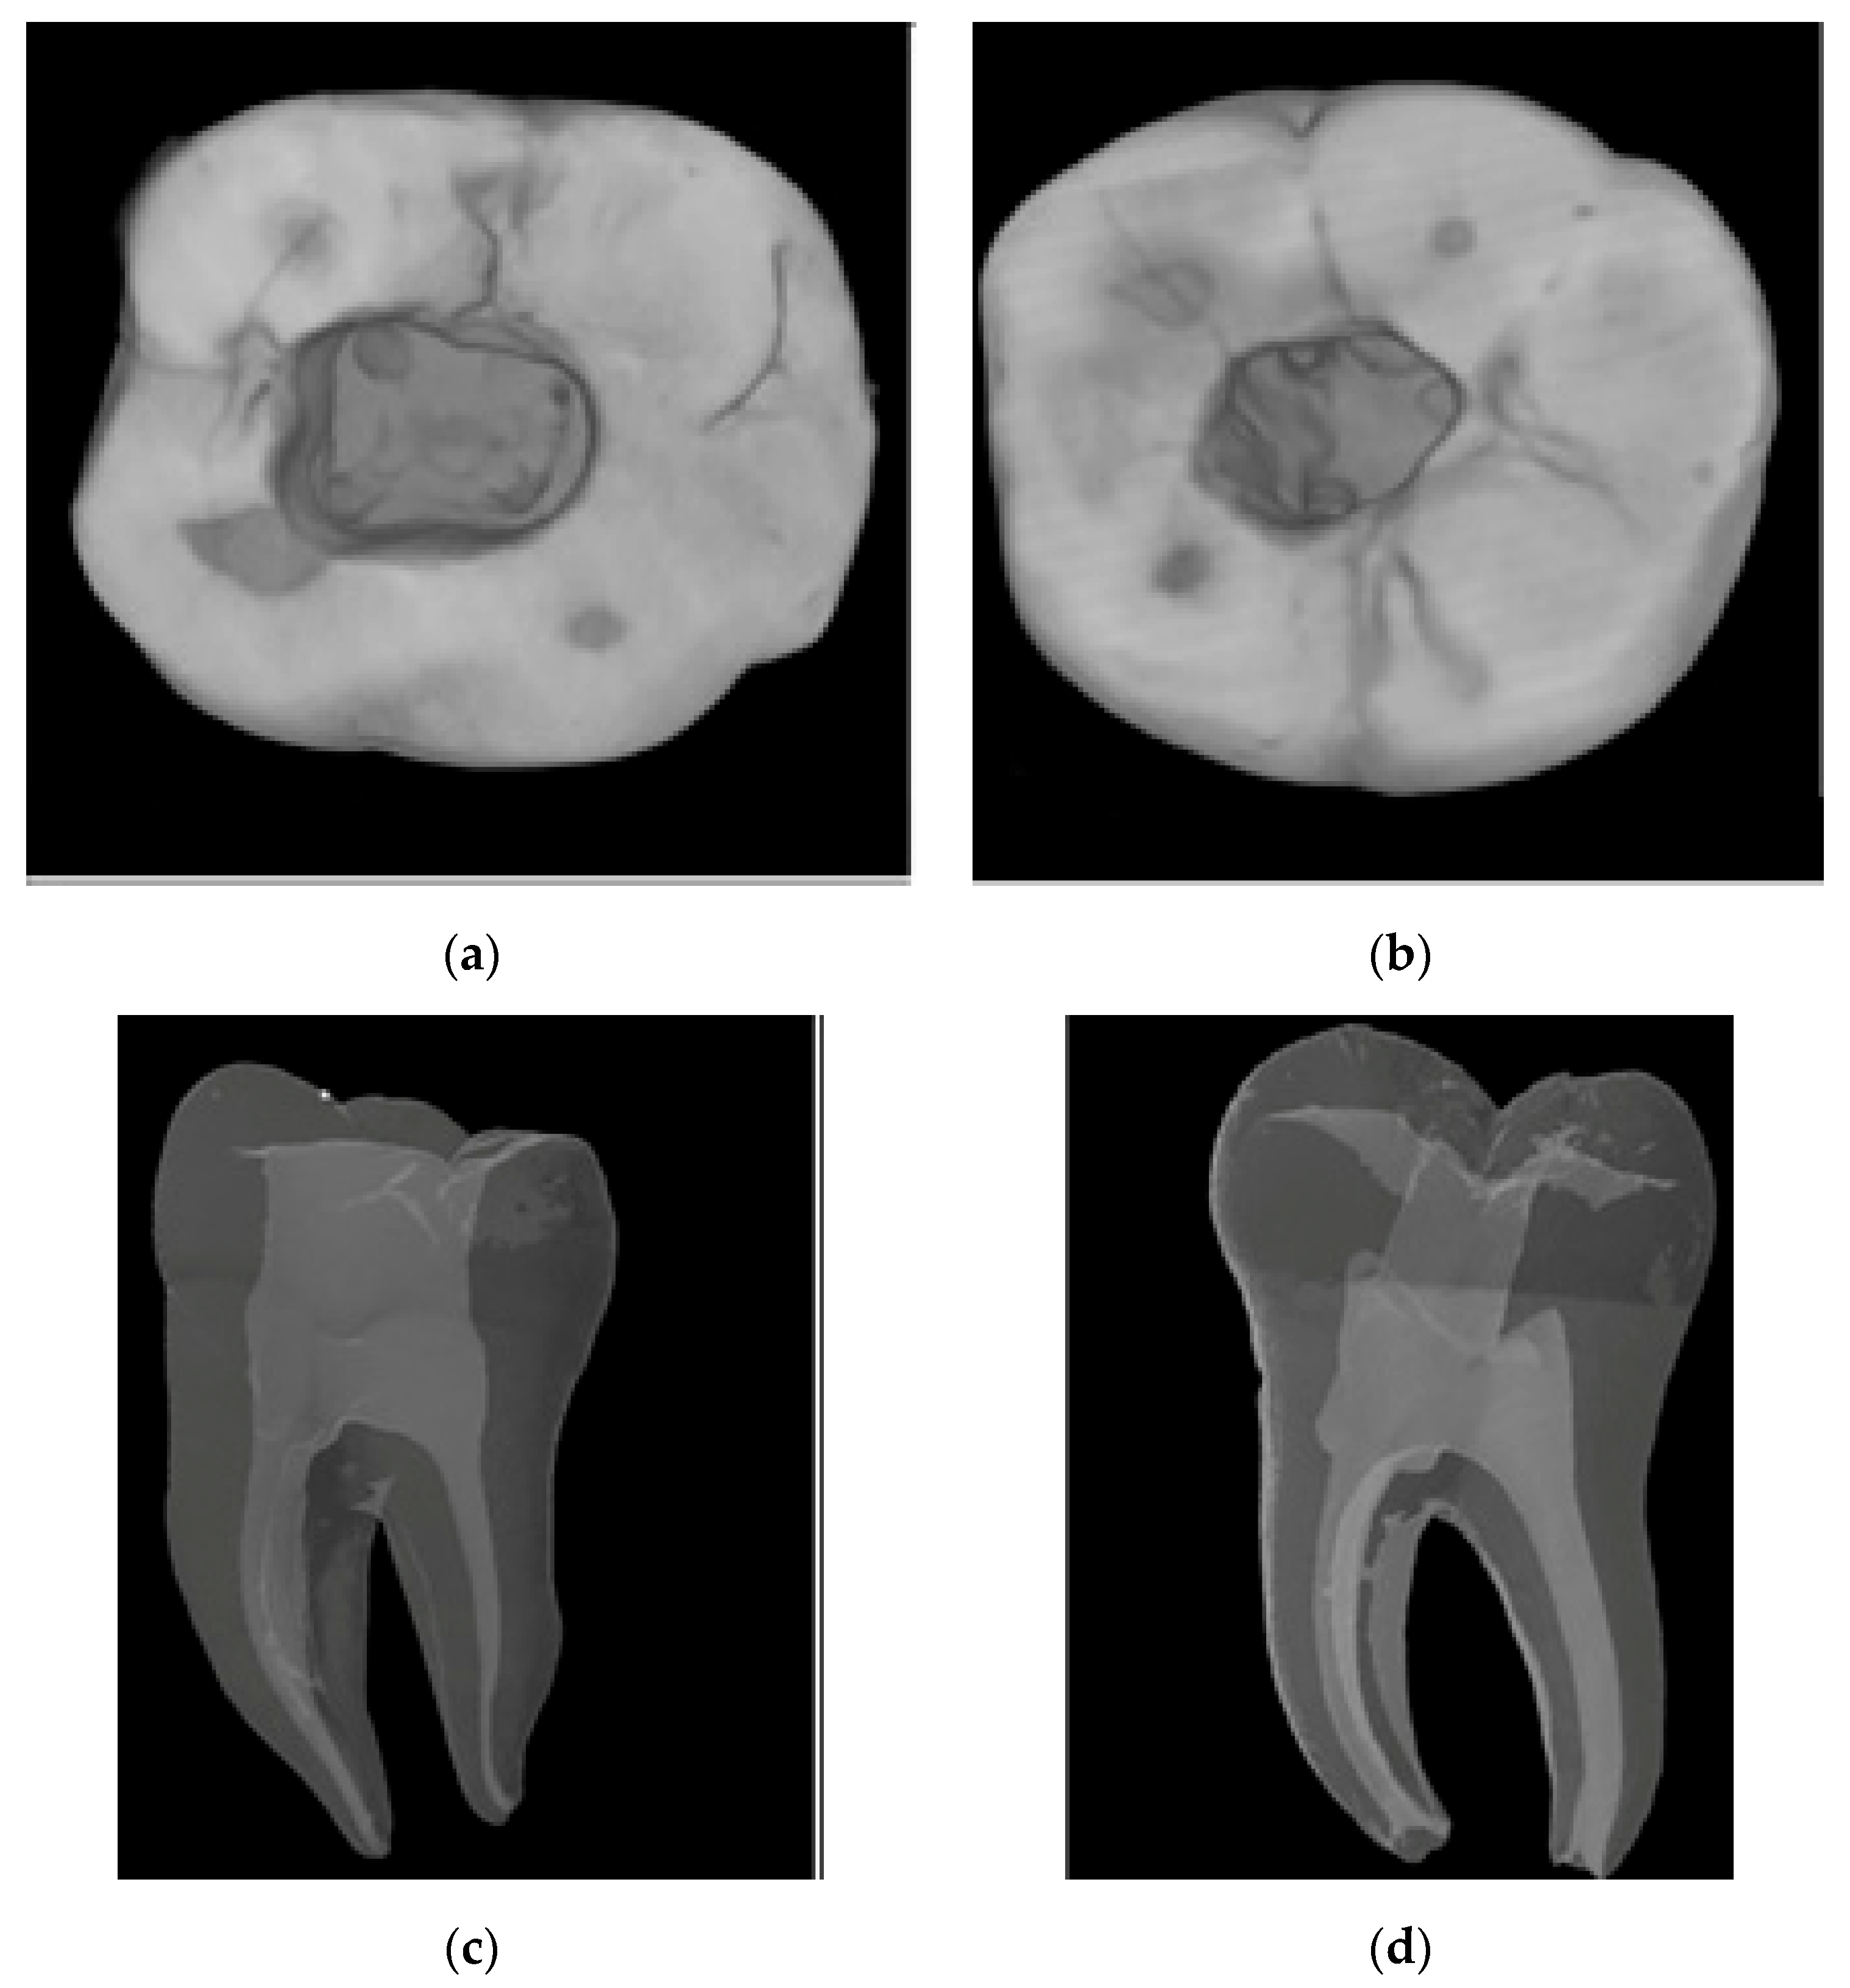

To conduct the first micro-CT scan before access cavity and root canal preparation, the samples were fixed on the turntable of the micro-CT device and scanned with the X-ray source of the device at 80 kVp, 125 mA, 26.7 μm pixel size, and 0.2 rotation. The images obtained after the scan were transferred to the NRecon software (ver. 1.6.10.4, Bruker X-ray, Kontich, Belgium). A total of 1800 two-dimensional sections were obtained from each sample. For the reconstruction, the ring artifact correction was fixed to 7, and the smoothing parameter was set to 3. The beam hardening artifact correction was set to 38%. Contrast settings were kept between 0 and 0.05 for all the samples. Examples of images obtained from micro-CT scanning before cavity and root canal preparation are given in Figure 1.

Figure 1 shows the results of the first micro-CT scan. In this scan, teeth were examined regarding fractures, cracks, caries, and radii of curvature to avoid missing possible errors in the dental operating microscope. Samples from micro-CT scanning were placed in silicone molds (Express XT, 3M ESPE, Neuss, Germany) with root tips visible to stabilize and isolate them from the environment during access cavity preparation. The experimental groups were formed according to the type of access cavity and the Ni–Ti file system to be used, as shown in Figure 2.

The images obtained after micro-CT scanning of traditional and conservative access cavities are shown in Figure 3. Figure 3 shows the differences between the access cavities of the two different methods.

Figure 3. Micro-CT images illustrate the differences between traditional and conservative access cavities. (a) Axial section of a traditional access cavity. (b) Axial section of a conservative access cavity. (c) Sagittal section of the conservative approach. (d) Sagittal section of the traditional approach.